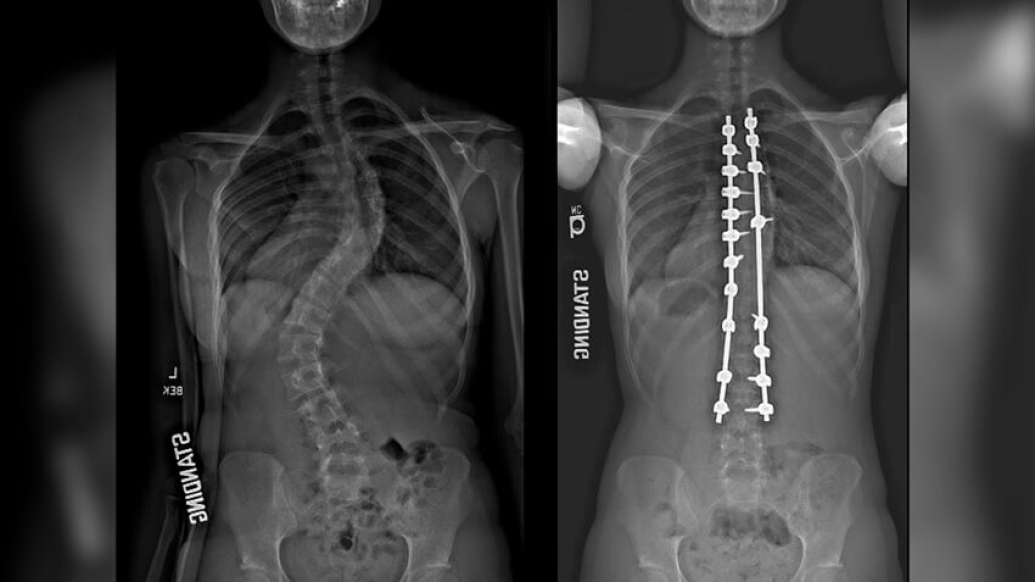

Xray image comparison of spine.

For a long time, the average length of stay after spinal fusion surgery for scoliosis, or a curve in the spine, was between four and five days. During that time, the adolescents who had rods and screws inserted to fuse their spines into a straighter position would receive narcotics either intravenously or through a catheter that went into the spinal canal after surgery.